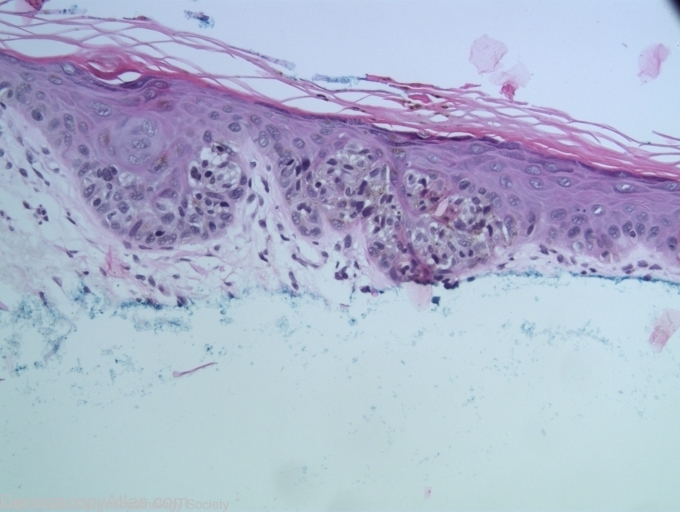

Diagnosis: Melanoma in situ

Description: Multiple brown dots and no network.

An elderly man presented for a check up when this pigmented lesion on his arm was noted. Other than the pigment dots there was little else to say this was melanocytic. The pathology showed melanoma in situ.